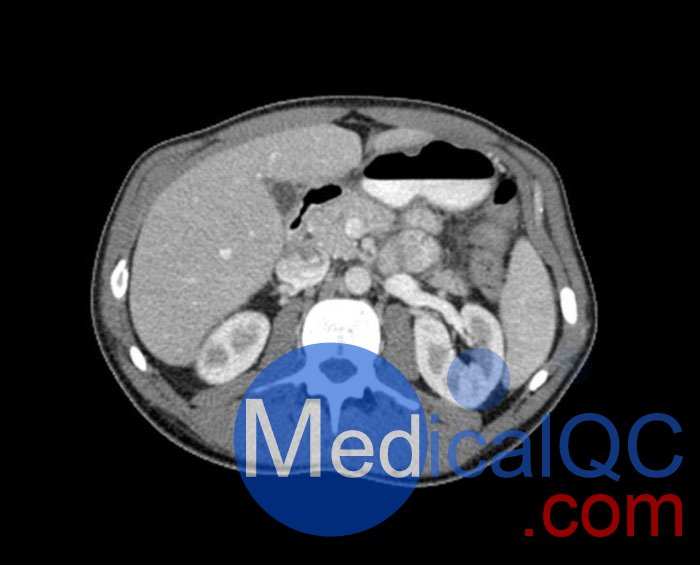

WEK57-01門靜脈期軀干模體,WEK57-01軀干模型模擬了門靜脈期的造影劑增強(qiáng)胸部、腹部和骨盆。它覆蓋了會陰的第二胸椎。

右側(cè)有髂淋巴結(jié)腫塊。

該模型可用于 CT(包括 CBCT)以評估和優(yōu)化成像性能和后處理應(yīng)用,包括支持 AI 的應(yīng)用。它也適用于培訓(xùn)目的。

該模型提供了對軟組織和骨組織的詳細(xì)而逼真的模擬。包括肺在內(nèi)的空隙充滿了大約 -160HU的纖維素聚合物復(fù)合材料。

真實模擬脈管系統(tǒng)、骨骼和軟組織,包括肺、心臟、肝臟、膽囊、胰腺、脾臟、腎上腺、腎臟、胃、小腸、結(jié)腸、膀胱和前列腺。

右側(cè)髂外淋巴結(jié)腫塊。

大?。?約 267 x 185 x 466 mm

重量: 約 11040 g

基材: 纖維素-聚合物復(fù)合材料

最佳管電壓: 120 kVp – 可根據(jù)要求進(jìn)行調(diào)整

WEK57-01門靜脈期軀干模體,WEK57-01軀干模型成像效果圖: